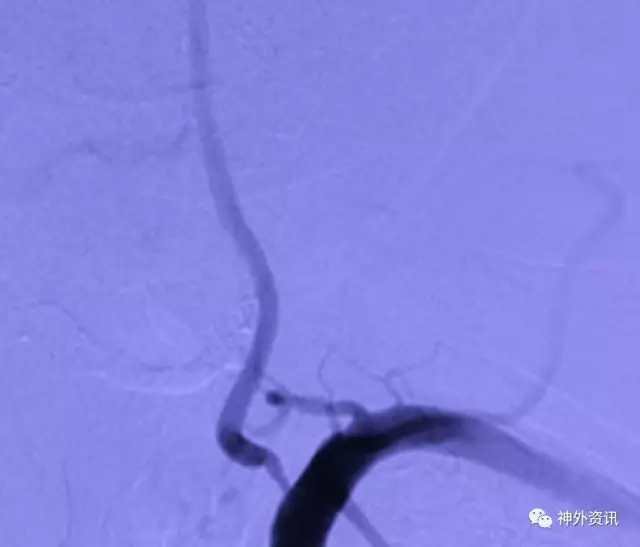

L一VA开口重度狭窄

L-VA正侧位:颅内段各血管显影尚好,左侧PⅠCA供血双侧

L一VA开口支架成形满意,术后病人症状缓解